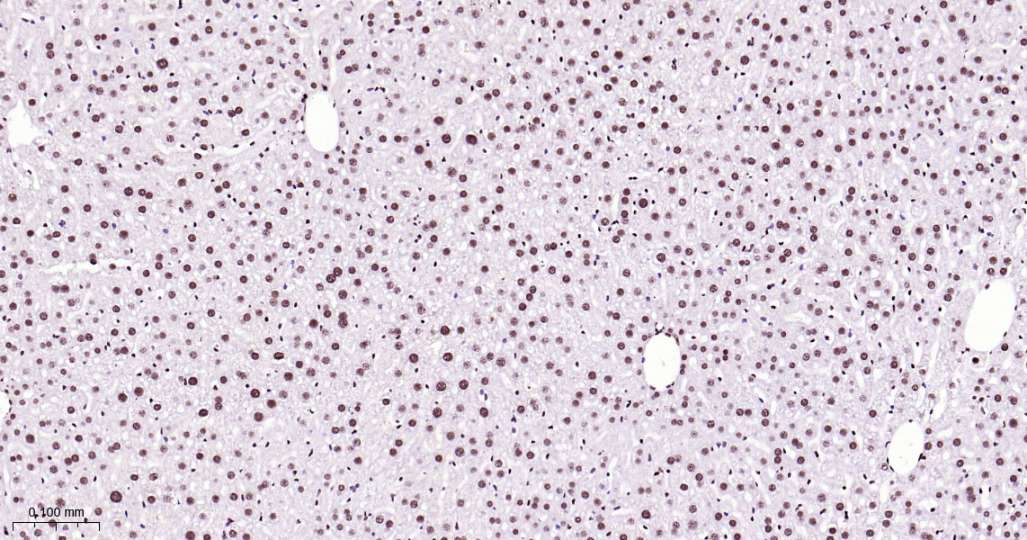

Immunohistochemical analysis of paraffin embedded Mouse liver tissue slide using IHC0615 (ILF3 Kit).